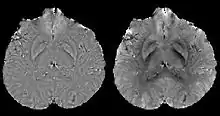

Estimated local field maps using left) high-pass filtering method, right) projection onto dipole fields (PDF) method.

In human brain quantitative susceptibility mapping, only the local susceptibility sources inside the brain are of interest. However, the magnetic field induced by the local sources is inevitably contaminated by the field induced by other sources such as main field inhomogeneity (imperfect shimming) and the air-tissue interface, whose susceptibility difference is orders of magnitudes stronger than that of the local sources. Therefore, the non-biological background field needs to be removed for clear visualization on phase images and precise quantification on QSM.

Ideally, the background field can be directly measured with a separate reference scan, where the sample of interest is replaced by a uniform phantom with the same shape while keeping the scanner shimming identical. However, for clinical application, such an approach is impossible and post-processing based methods are preferred. Traditional heuristic methods, including high-pass filtering, are useful for the background field removal, although they also tamper with the local field and degrade the quantitative accuracy.

More recent background field removal methods directly or indirectly exploit the fact that the background field is a harmonic function. Two recent methods based on physical principles, projection onto dipole fields (PDF)[8] and sophisticated harmonic artifact reduction on phase data (SHARP),[9] demonstrated improved contrast and higher precision on the estimated local field. Both methods model the background field as a magnetic field generated by an unknown background susceptibility distribution, and differentiate it from the local field using either the approximate orthogonality or the harmonic property. The background field can also be directly computed by solving the Laplace's equation with simplified boundary values, as demonstrated in the Laplacian boundary value (LBV) method.[10]